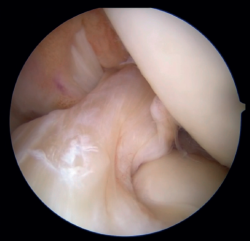

Figura 6. Imagen final de la reparación tras la colocación del InternalBrace® con cinta de alta resistencia. Rodilla izquierda, visión desde el portal anterolateral.

Es importante confirmar bajo visión artroscópica la tensión del LCA tanto en el rango de movimiento completo como con el uso de palpador y las maniobras de Lachmann y cajón anterior (Figura 6).